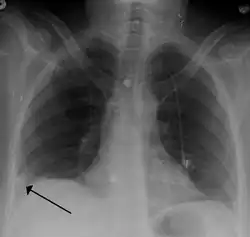

Low probability diagnostic tests/non-diagnostic tests

- Chest X-rays are often done on people with shortness of breath to help rule out other causes, such as congestive heart failure and rib fracture. Chest X-rays in PE are rarely normal,[70] but usually lack signs that suggest the diagnosis of PE (for example, Westermark sign, Hampton's hump).